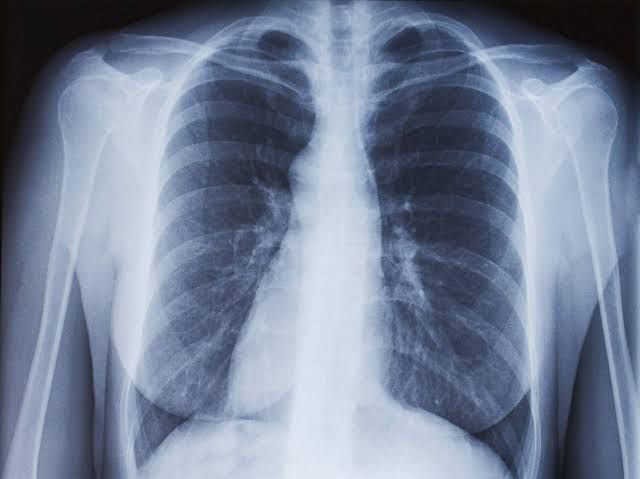

The main symptoms of a chest infection can include: a persistent cough coughing up yellow or green phlegm (thick mucus), or coughing up blood breathlessness or rapid and shallow breathing wheezing a high temperature (fever) a rapid heartbeat chest pain or tightness feeling confused and disorientated You may also experience more general symptoms of an infection, such as a headache, fatigue, sweating, loss of appetite, or joint and muscle pain.